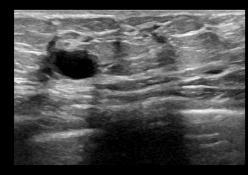

the structuring component while removing all other foreground pixels. An image's internal noise is removed using the opening technique. The first step in the opening processiserosion,followedbydilation. (a) (b) (c) (d) Fig3.(a)NLM denoisedBUS image andBinarized image (d)Dilation operation

(b)Multi erodedimage (c) Opening operation

The NLM denoised image and its associated binarized image are shown in Figure 3(a). Figure 3(b) depicts the outcome of repeated erosion operations. The majority of superfluous artefacts and artefacts are eroded withsuccessiveerosion.

The result of the opening procedure, followed by erosion, is shown in Figure 3 (c). The remaining noise was removed using the opening procedure while the image's essentialfeaturewaspreserved.

The size and shape of the artifacts have shrunk as a result of the successive erosion. Apply consecutive dilation with the same number of times erosion is applied to roughly recover their size. Furthermore, the same structuring elementisusedtoensurethatthecontourofthefeaturesis restored as closely as feasible to the original. The result of thedilationprocedureisshowninFigure3(d).